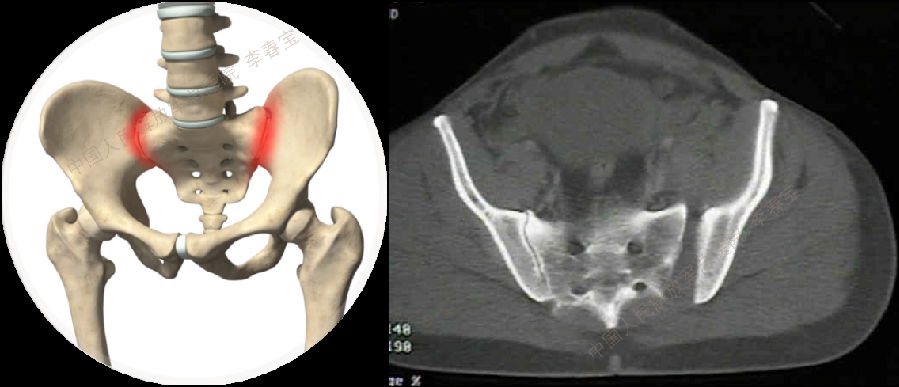

7. 骶髂关节扭伤

骶髂关节是微动关节,运动不当可以发生韧带扭伤,并且多发于腰骶韧带。主要症状:骶髂关节疼痛并向大腿后方和腘窝部放射,检查时骨盆挤压和分离试验阳性,应于腰椎间盘突出相鉴别。治疗:腰围支具固定;封闭;理疗、手法按摩。